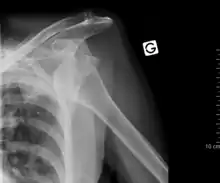

Luxación de hombro

Luxación es la lesión en la cual los segmentos óseos que forman una articulación se separan. La luxación de hombro, o luxación escapulohumeral ocurre con frecuencia debido a la gran amplitud de movimientos que presenta esta articulación. Generalmente es una luxación anterior, es decir la cabeza del húmero se sale de su posición normal en la cavidad glenoidea de la escápula y se coloca delante, haciendo muy difícil y doloroso cualquier tipo de movimiento en el que deban desplazarse estos elementos óseos. Suele ocurrir por un traumatismo, siendo muy frecuente en la práctica deportiva. El tratamiento requiere la colocación mediante maniobras especiales del humero en su lugar correcto, no debe nunca intentar realizarse esta acción por personas que no sean profesionales sanitarios.[2]

Fracturas del cuello del húmero

EL cuello del húmero está situado próximo a la articulación escápulohumeral. Este tipo de fracturas son frecuentes en niños y pacientes mayores de 50 años y pueden afectar según su localización al cuello anatómico del húmero o al cuello quirúrgico. En la mayor parte de los casos se producen como consecuencia de un mecanismo indirecto, por ejemplo una caída en la que el sujeto apoya la mano en el suelo con el miembro superior extendido. Menos frecuentemente el mecanismo es directo por un golpe directo sobre la zona, pues la región del hombro está bien protegida por diferentes músculos, como el deltoides, que actúan amortiguando los impactos.